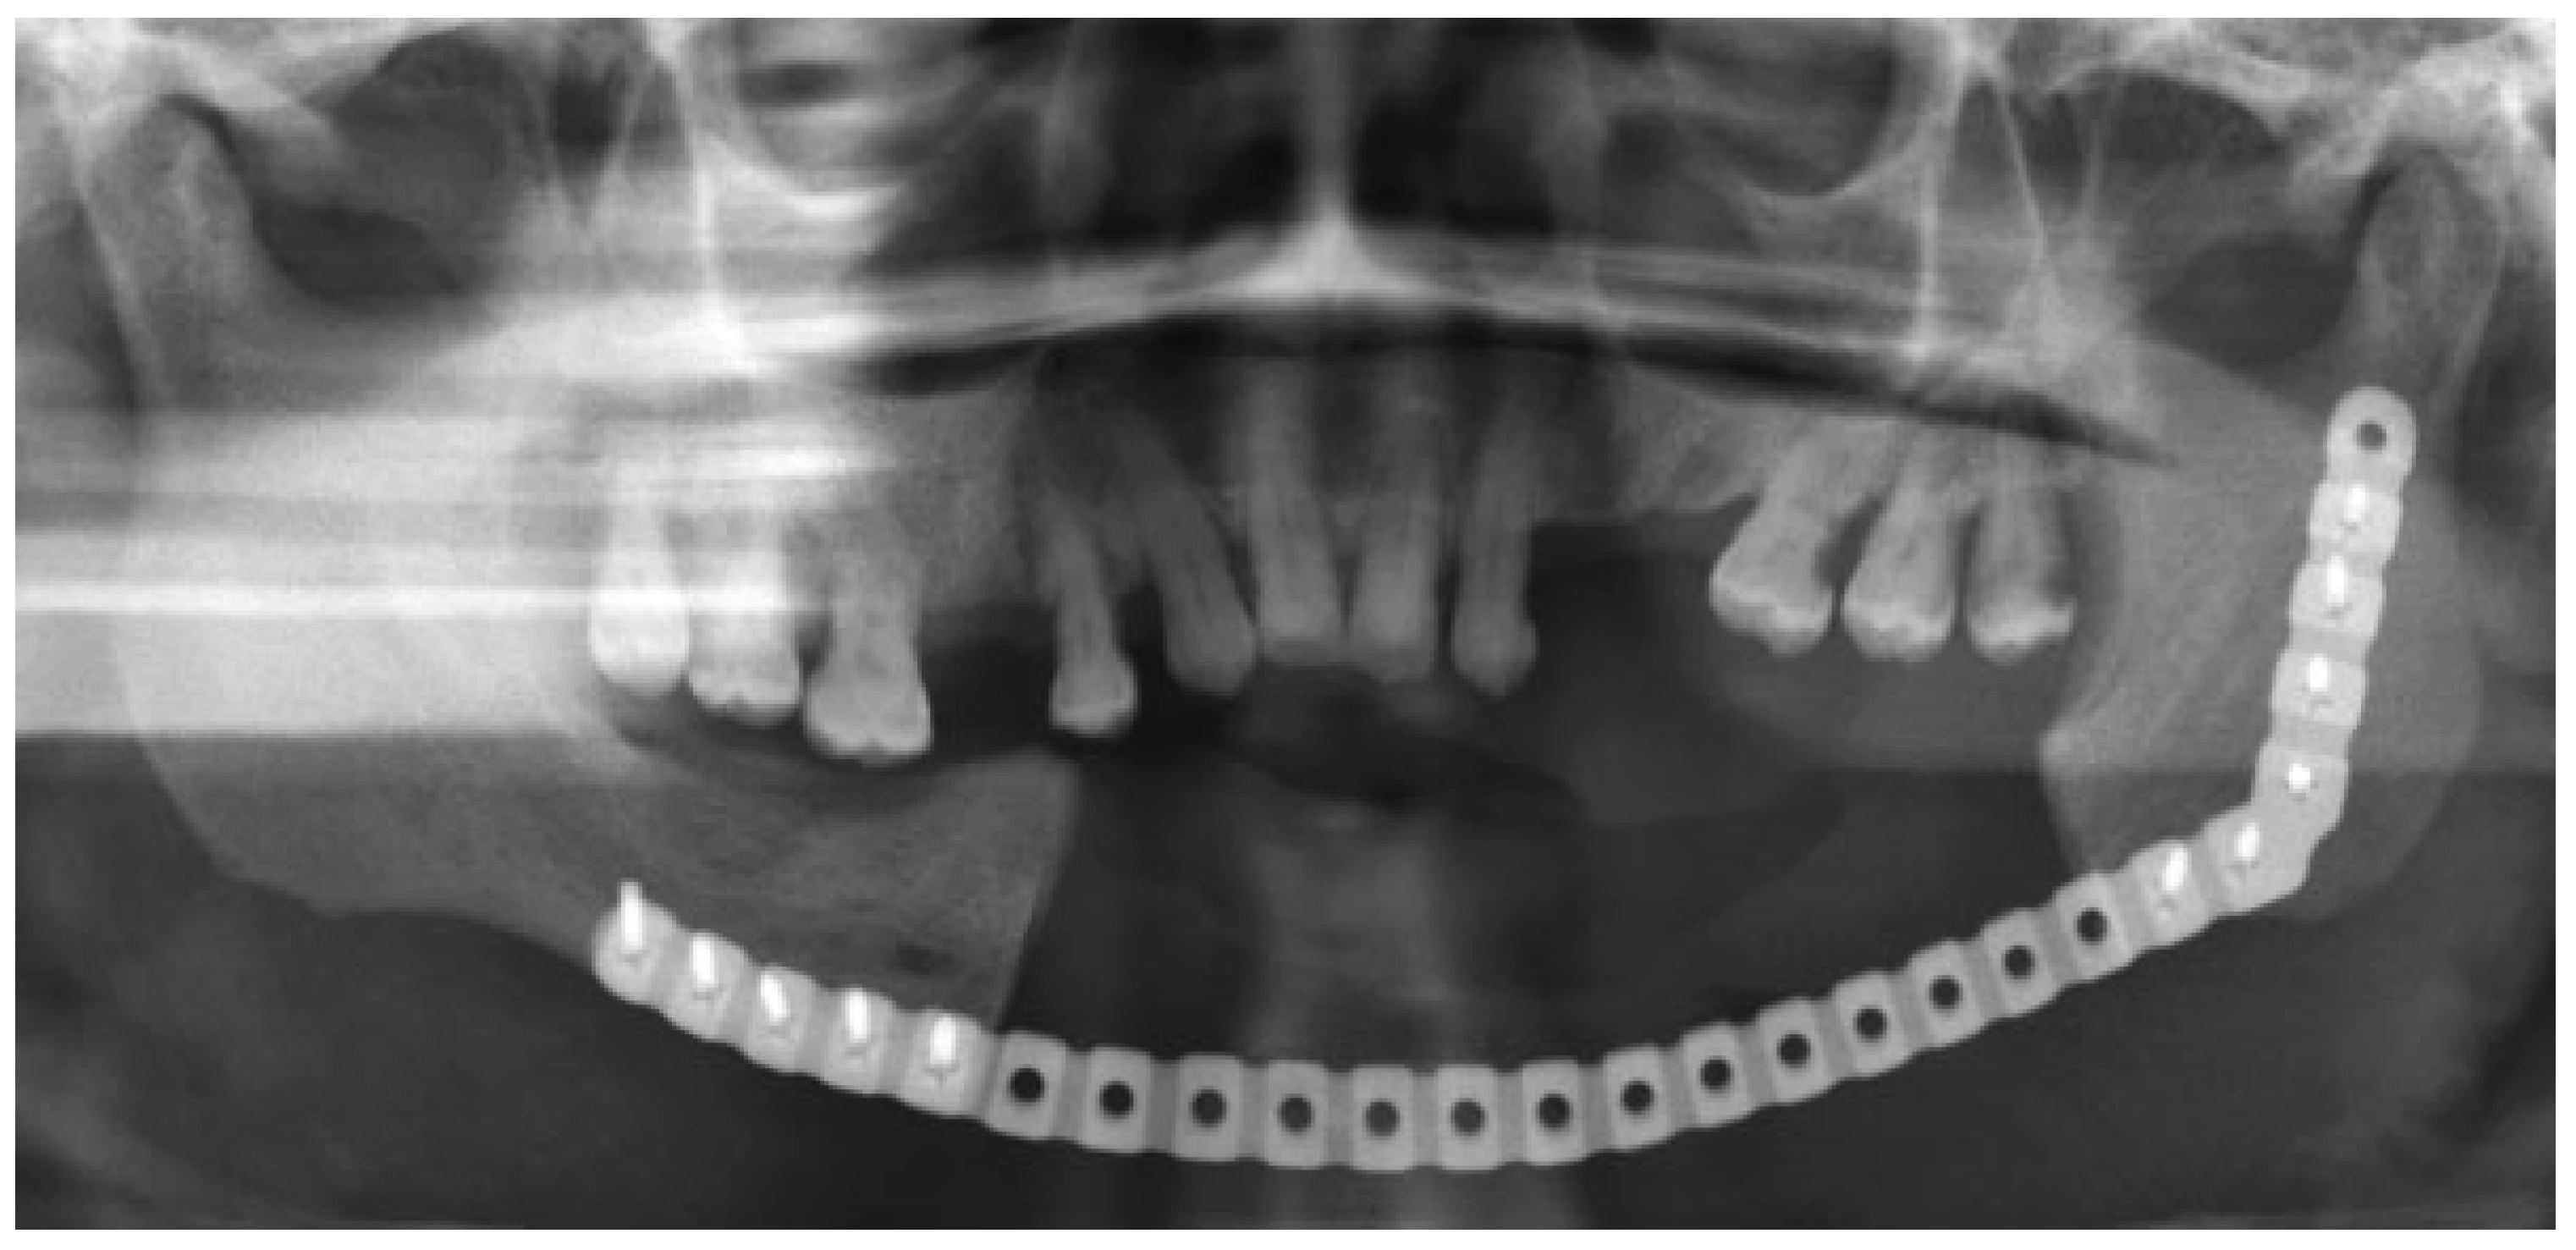

The third case was a 29-year-old white male with an expansile lesion of the anterior mandible. Panoramic radiograph showed a multilocular lesion involving the inferior border of the mandible and extending from the left second molar to the right canine (Figure 1). Incisional biopsy proved this lesion to be an ameloblastoma. The treatment plan included mandibular resection with 1-cm margin and immediate reconstruction with a free fibula microvascular flap. A tracheostomy for airway protection was also planned. A high-resolution CT scan was obtained followed by construction of a model. A custom prebent plate was obtained using the model as a reference. Using a combined transoral and transcutaneous approach, the mandible was resected from the left angle through the right second bicuspid. The 2.4-mm prebent reconstruction plate was placed (Figure 2). A free microvascular fibula flap with a skin pedicle was harvested. The fibula was contoured and adapted to the inner aspect of the custom-bent plate and secured with nonlocking screws (Figure 3). The skin pedicle was used to close the resulting soft tissue defect at the floor of the mouth. A tracheostomy was performed at the end of the case. The total surgical time including all the procedures was 10 hours and 33 minutes.

Figure 3. Postoperative panoramic radiograph. Reconstruction plate with free microvascular fibula graft in place, secured to the plate. Case 3.